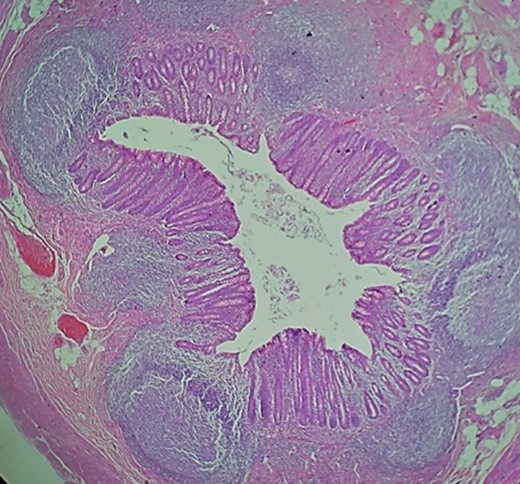

Surgery was straightforward from this point. The toothpicks were carefully removed, an appendectomy was performed, and the perforation at the base of cecum was repaired with an absorbable suture and covered with an omental patch. An extensive washout with saline solution was carried out and the remainder of the procedure was completed without complications (Fig. 4).

Pathology, appendix wall with acute mucosal inflammation and neutrophilic infiltrates in its wall.